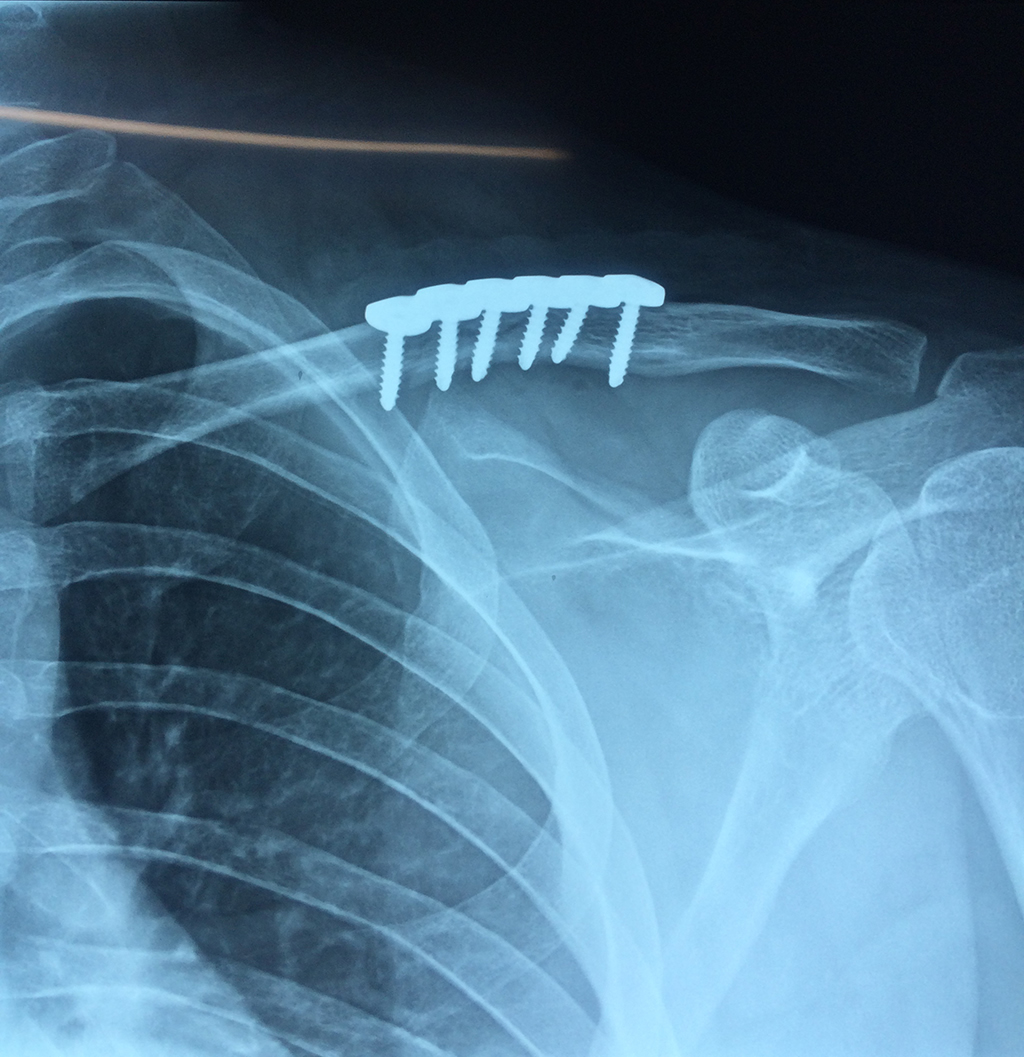

Cirugias en El Salvador - Clavícula

La clavícula es un hueso largo, con forma de "S" itálica, situado en la parte anterosuperior del tórax. Junto con la escápula forman la cintura escapular. Se puede palpar por toda su longitud y se extiende del esternón al acromion de la escápula, siguiendo una dirección oblicua lateral y posterior.